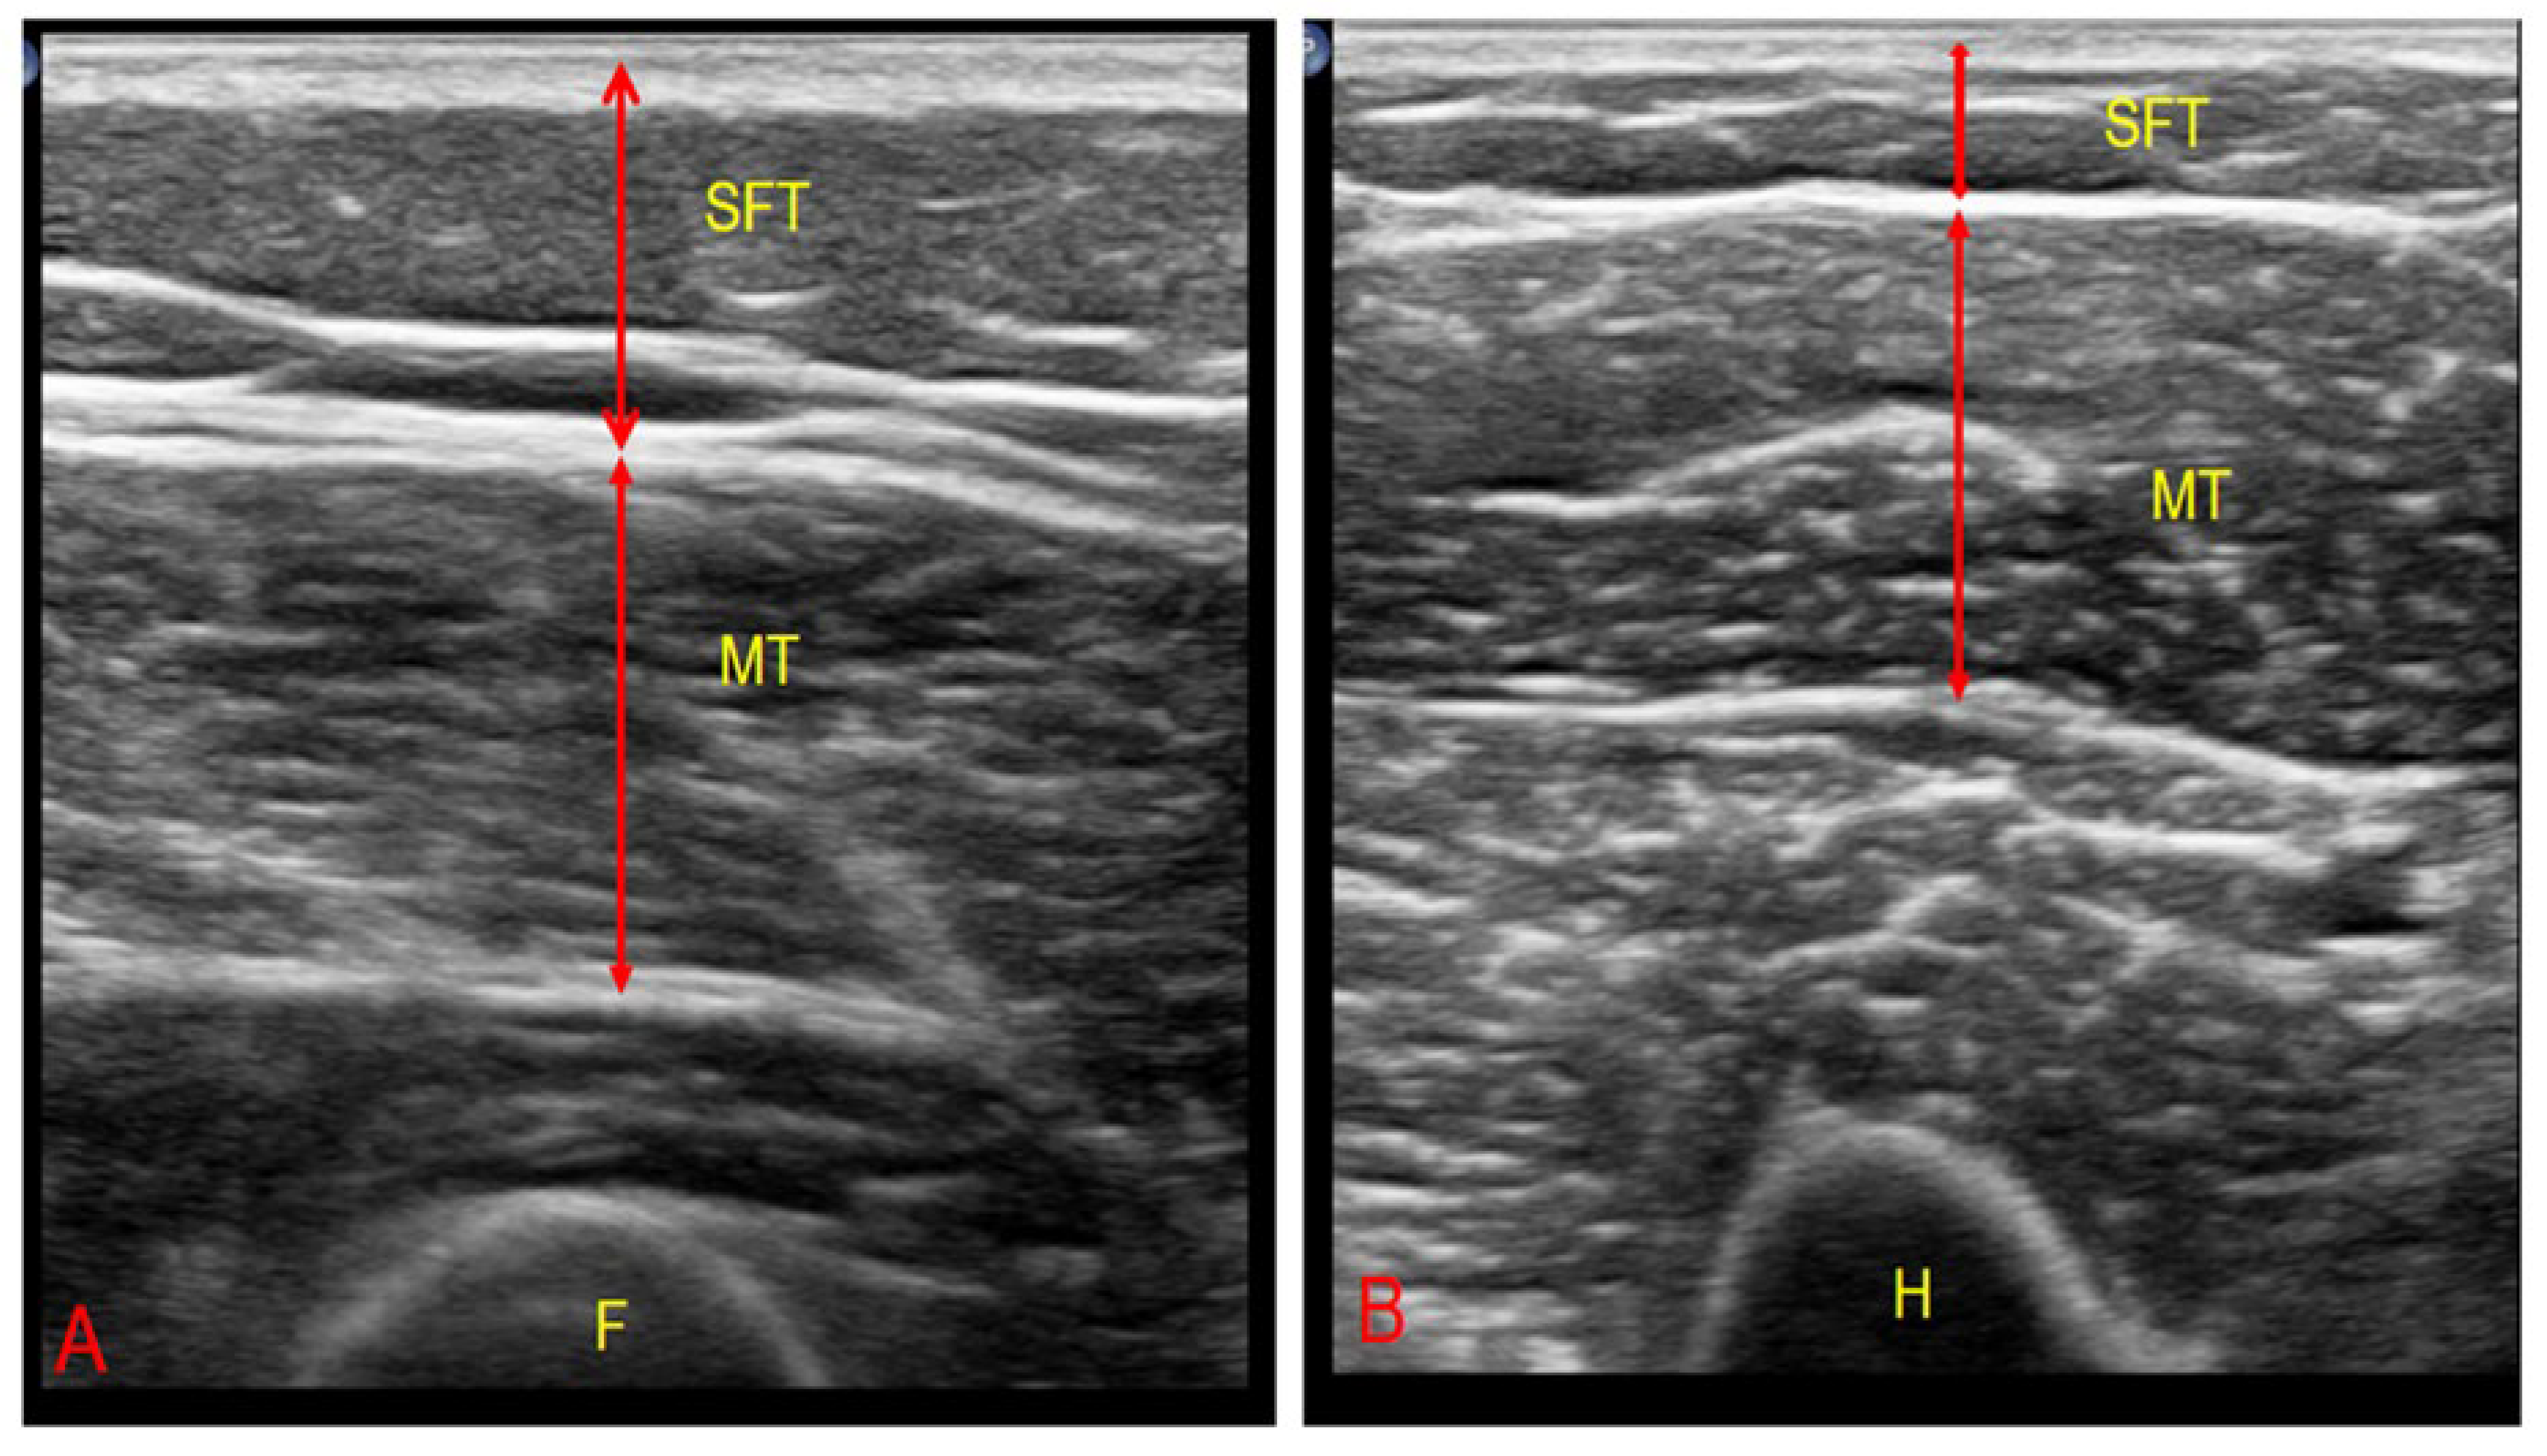

2.4.3. Ultrasonographic Muscle–Fat Ratio

| SFT | Subcutaneous fat thickness |

| RF-MT | Rectus femoris muscle thickness |

| RF-MT/SFT | Rectus femoris muscle thickness to subcutaneous fat thickness ratio |

| RF-SFT | Rectus femoris subcutaneous fat thickness |